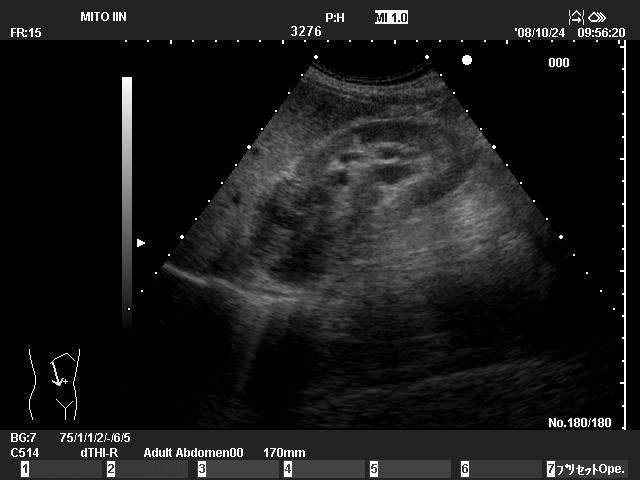

壮年男性の右

腎癌。淡明細胞癌。ステージは

pT3bN0M0

腎摘出にて

経過良好。